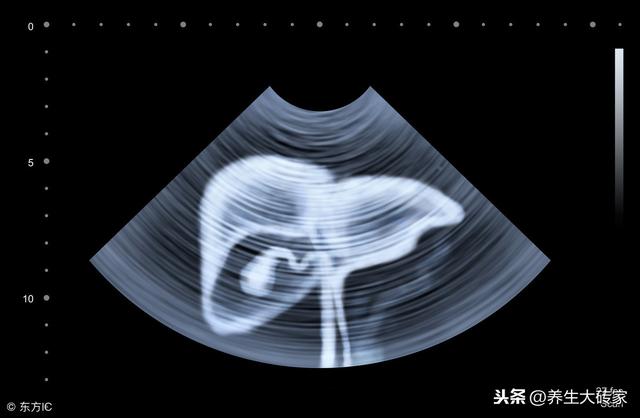

ÄÇÊÇÒòΪ £¬ Ò»µ© £¬ ¸ÎÔàÊÜË𠣬 ¸ÎÔ๦ÄÜÊÜÏÞ £¬ ¾Í»áÓ°Ïì¸ÎÔàÅŶ¾ÄÜÁ¦ ¡£

ÈÕ»ýÔÂÀÛ £¬ ±ã»áµ¼Ö¸ÎÔàÎÞ·¨¼°Ê±ÅųýÌåÄÚ¶¾ËØ £¬ ¶ø¡°ÖÍÁô¡±ÔÚ¸ÎÔà £¬ µ¼Ö¸ÎÔà²Ø¶¾ £¬ Σº¦¸ÎÔà¡ø½¡¿µ¡ø¡£

----Ò»µ© £¬ ³öÏÖ4´ó¡°¼£Ïó¡± £¬ Ê®Óа˾ŸÎÒѲض¾ £¬ ¼òµ¥3ÕÐ £¬ ¸ø¸ÎÏ´Ï´Ôè//---- http://www.easyfang.com //